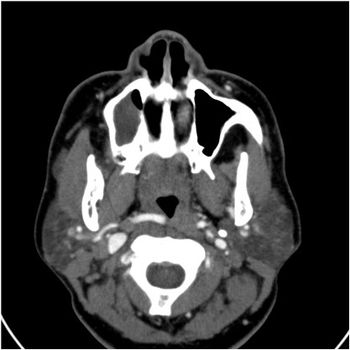

A new magnetic resonance spectroscopy technique provides a definitive diagnosis of brain cancer based on imaging of a protein associated with a mutated gene.